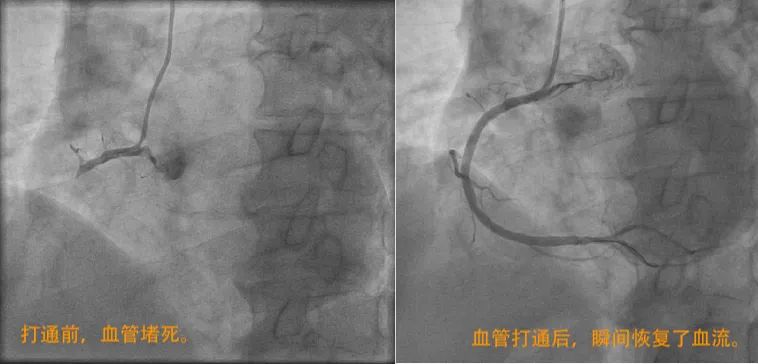

情况十分紧急,心内科任浩进主任立即带领团队为老人进行全面评估,发现老人的右冠状动脉近段急性闭塞伴血栓形成,必须尽快手术,否则随时会有猝死风险。在心内科团队医护人员的密切配合下,迅速使用血栓抽吸和支架开通闭塞的右冠状动脉,成功将何老伯从死亡线上拉回。术后,他的各种不适明显好转。